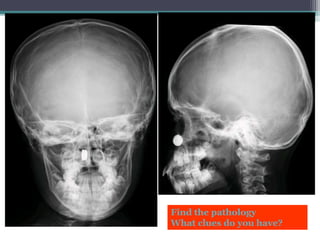

Find the pathology

What clues do you have?